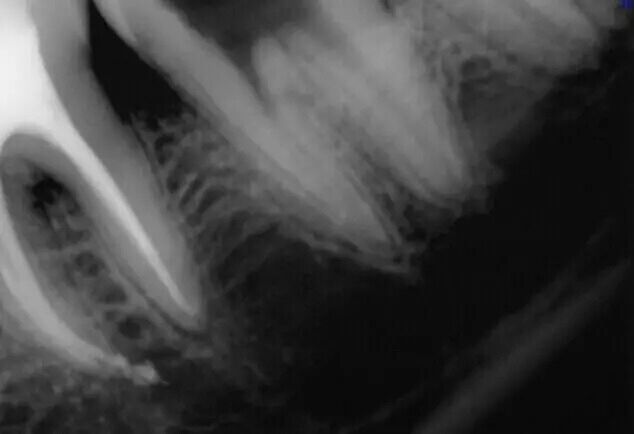

然后根充